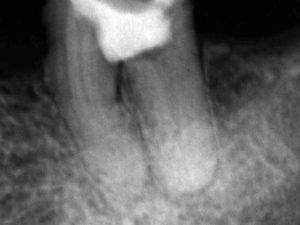

A proservação foi realizada após dois meses, observando neoformação óssea na região de furca e ausência de sintomatologia (figura 7).